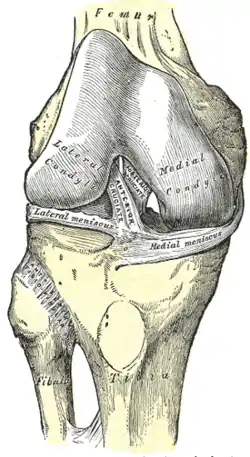

The lateral meniscus is grooved laterally for the tendon of the popliteus, which separates it from the fibular collateral ligament.

Its anterior end is attached in front of the intercondyloid eminence of the tibia, lateral to, and behind, the anterior cruciate ligament, with which it blends; the posterior end is attached behind the intercondyloid eminence of the tibia and in front of the posterior end of the medial meniscus.

The anterior attachment of the lateral meniscus is twisted on itself so that its free margin looks backward and upward, its anterior end resting on a sloping shelf of bone on the front of the lateral process of the intercondyloid eminence.

Close to its posterior attachment it sends off a strong fasciculus, the ligament of Wrisberg, which passes upward and medialward, to be inserted into the medial condyle of the femur, immediately behind the attachment of the posterior cruciate ligament.

The lateral meniscus gives off from its anterior convex margin a fasciculus which forms the transverse ligament.

Left knee joint from behind, showing interior ligaments. Right knee-joint, from the front, showing interior ligaments.

Right knee-joint, from the front, showing interior ligaments. Capsule of right knee-joint (distended). Lateral aspect.